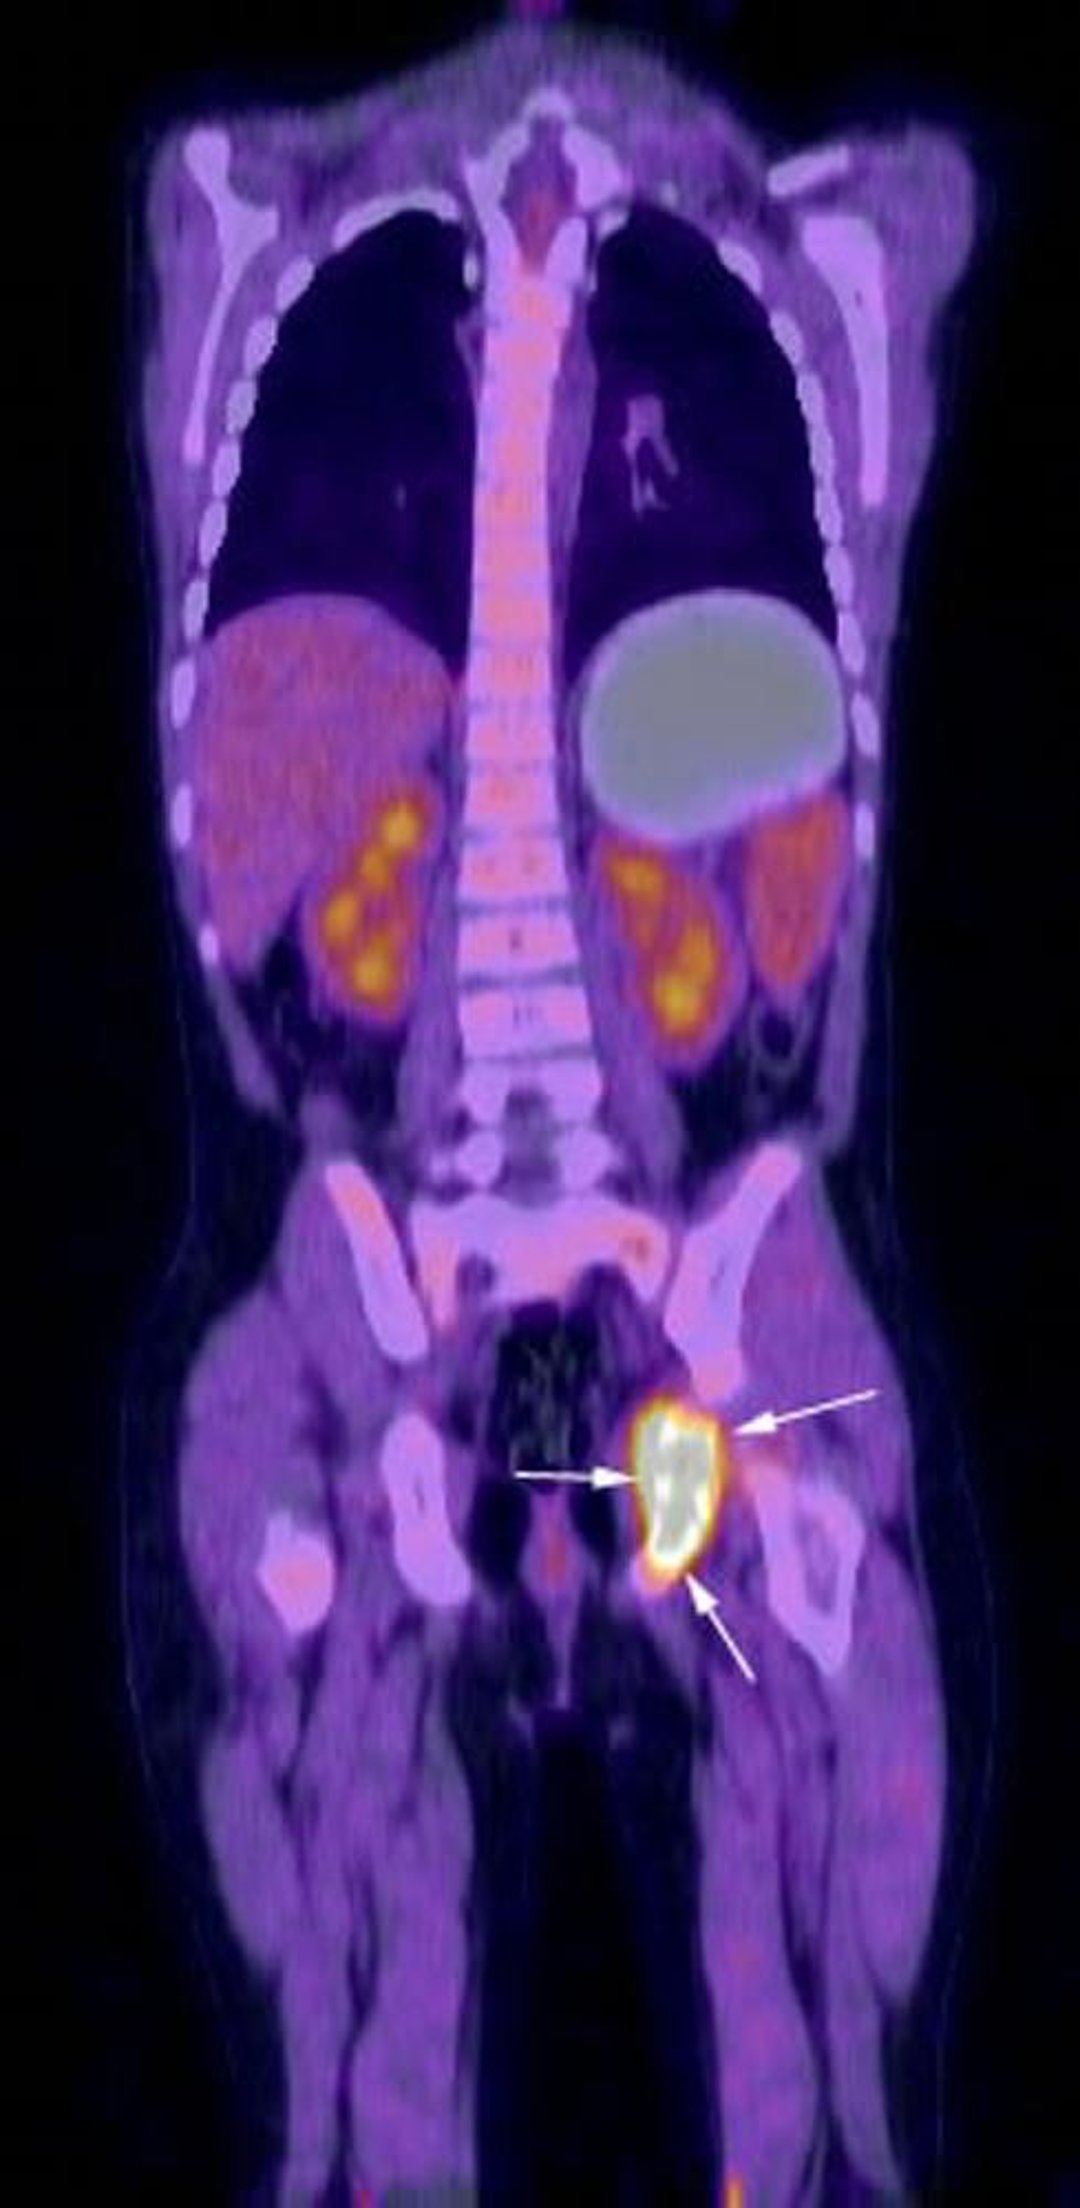

Hình ảnh tái tạo theo mặt phẳng đứng ngang từ kiểm tra bằng FDG-PET-CT cho thấy hoạt động trao đổi chất mạnh mẽ ở vùng ischium bên trái (các mũi tên) tương ứng với mô bào huyết tế bào Langerhans đã biết của bệnh nhân.

Hình ảnh do bác sĩ Hakan Ilaslan cung cấp.